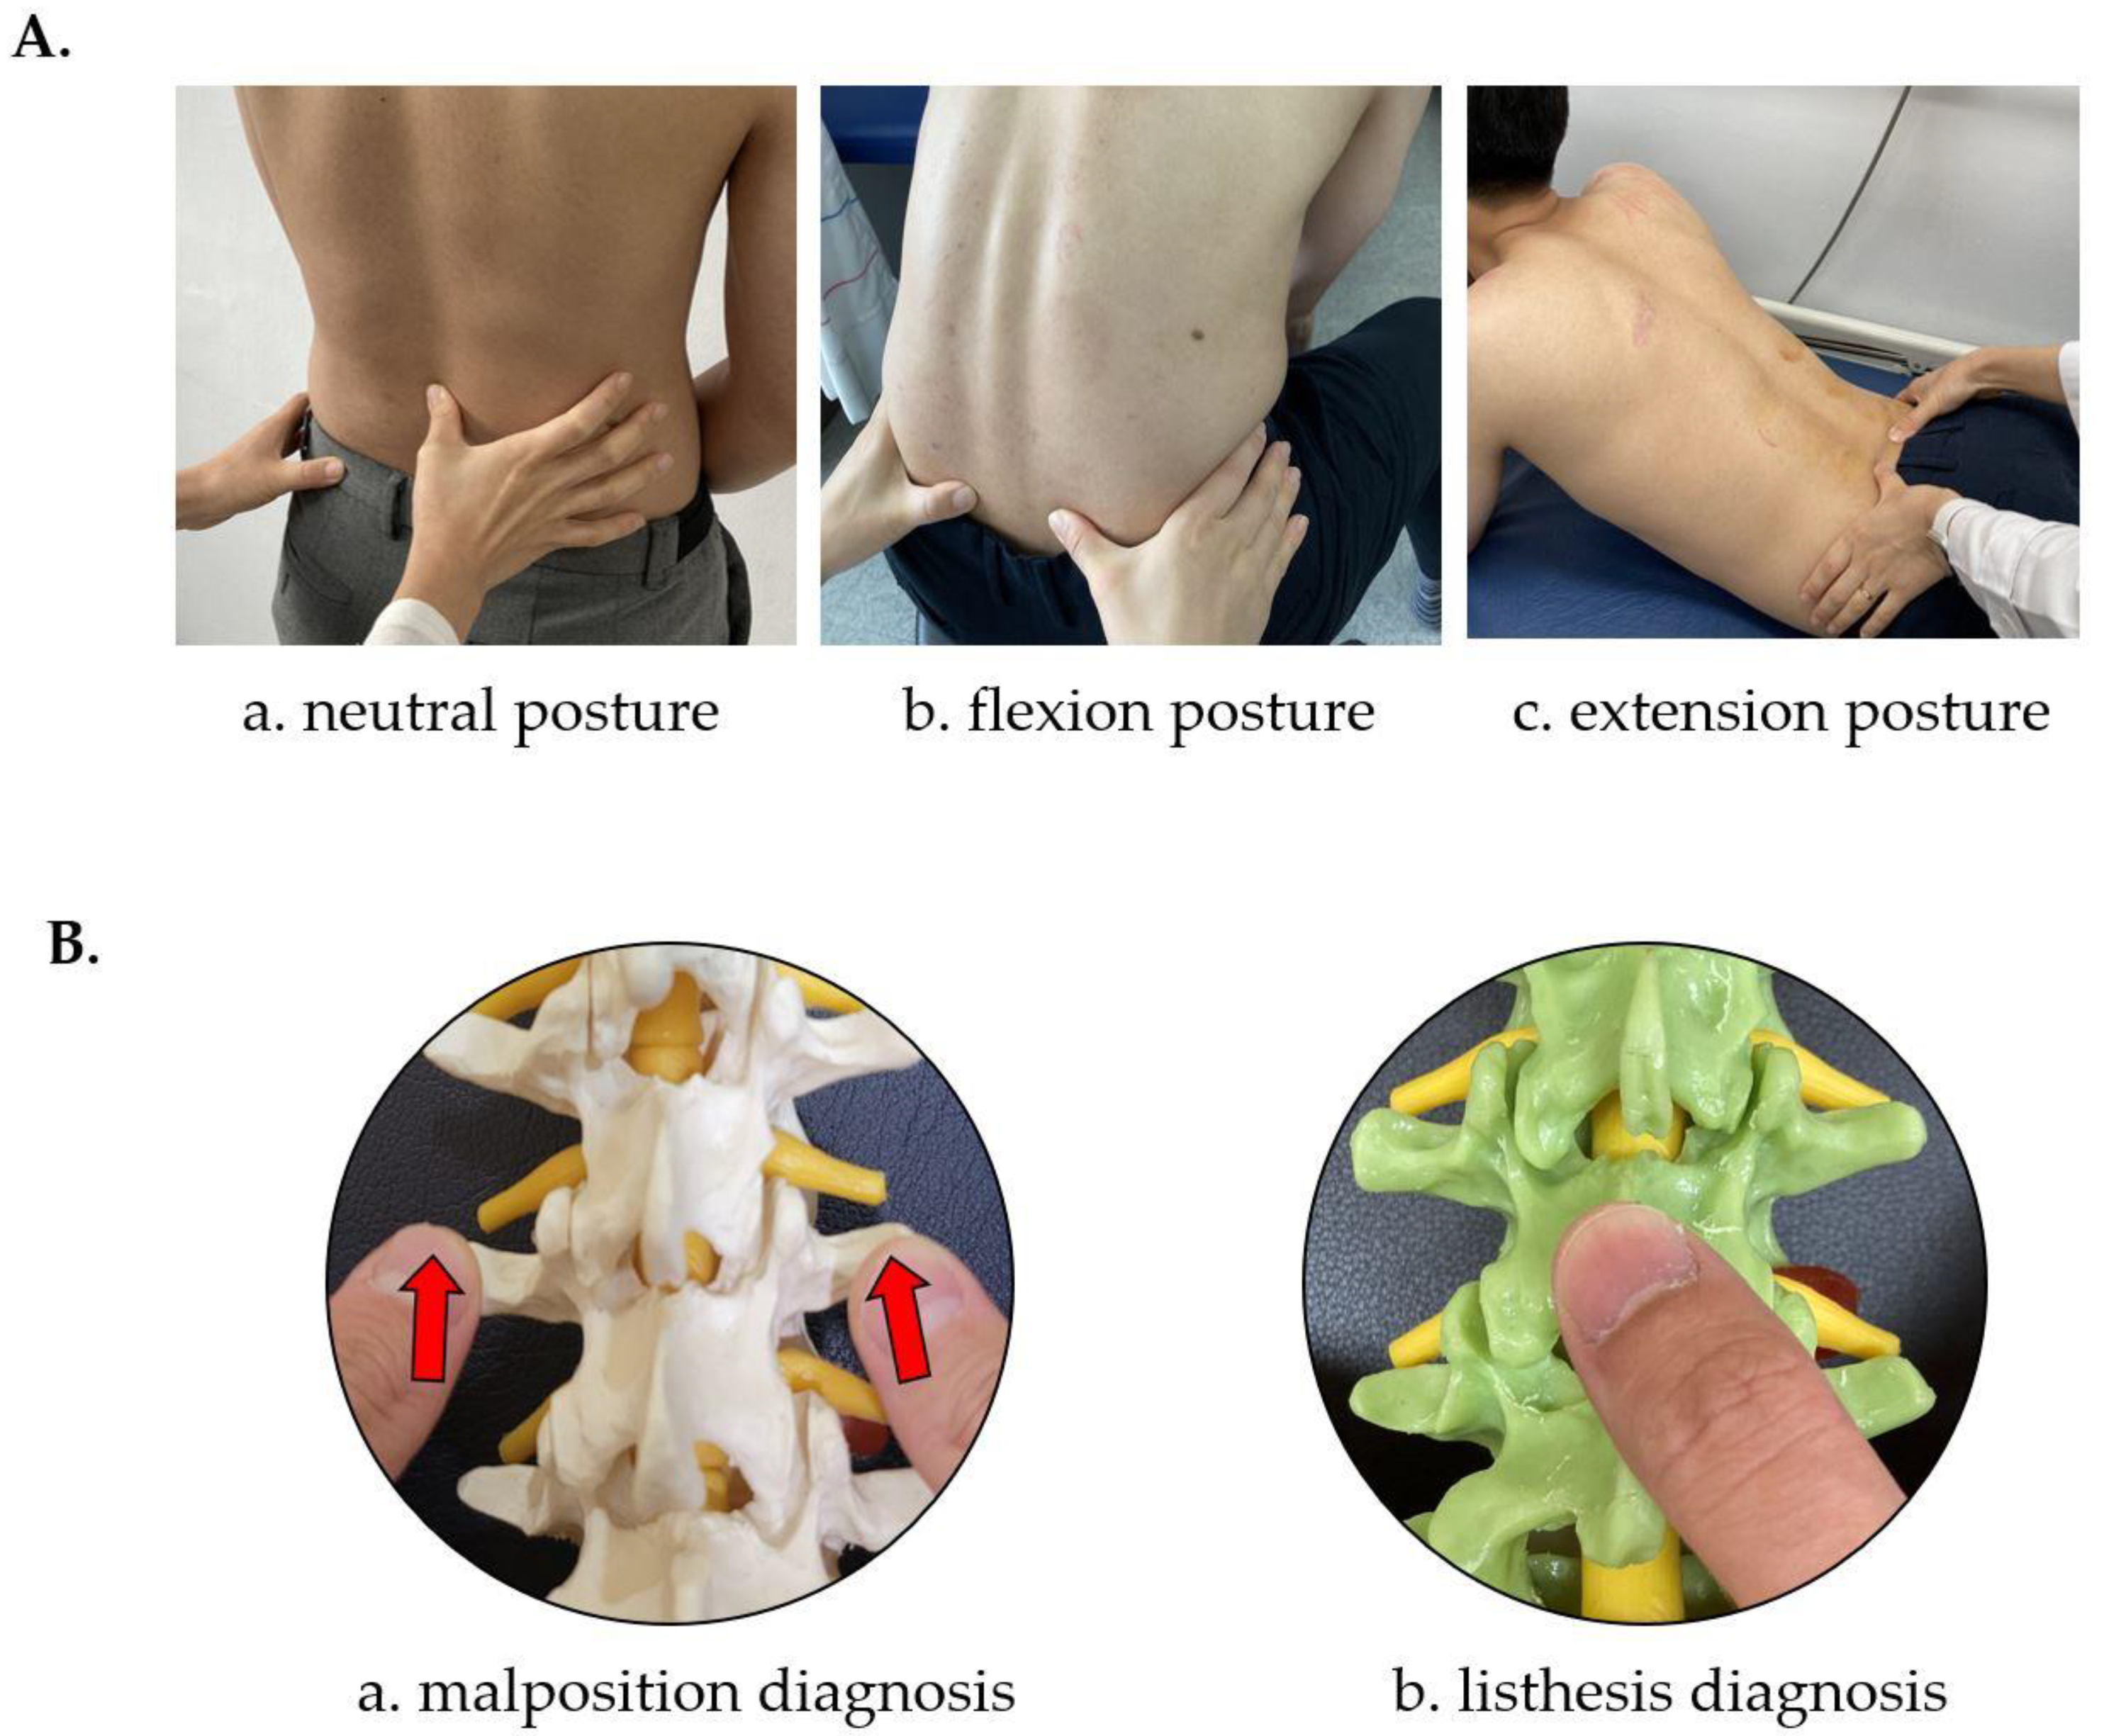

2.6.2. CMT Manual Diagnostic Method

2.6.3. CMT X-ray Image-Based Diagnostic Method